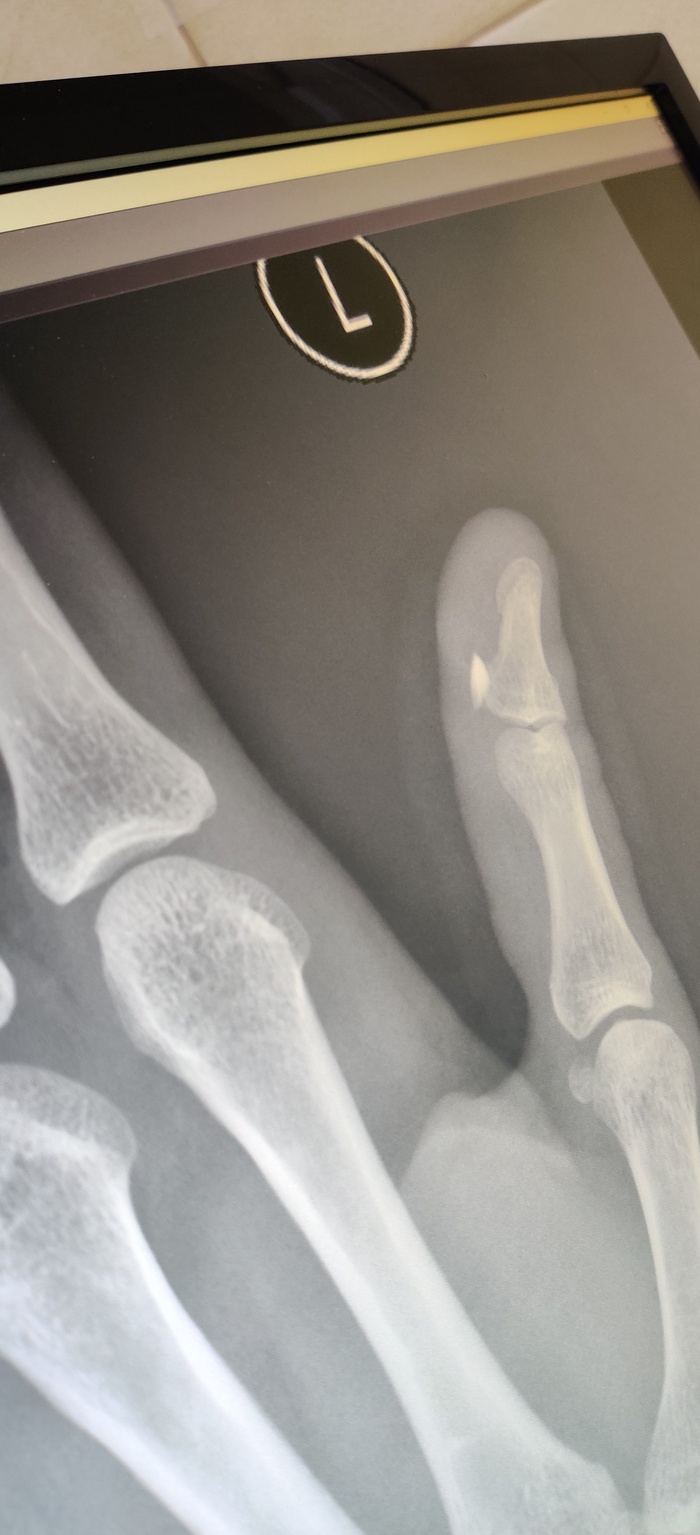

На рентгеновском снимке осколок стекла в пальце.

Было принято решение делать повторный рентген.

На нем обнаружились осколки меньшего размера.